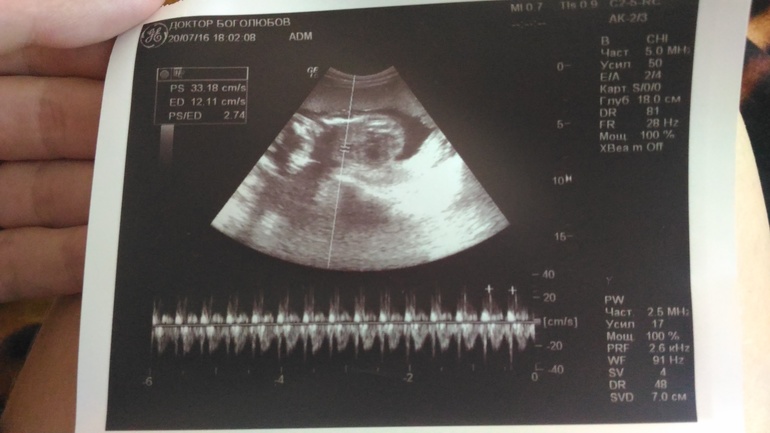

Яна в Благополучная беременность 9 лет Что хотел показать мне на этом снимке узист? СПАСИБО, ПОНЯЛА))) УЗИ, КТГ, доплер Посмотрите еще 20 записей на эту тему Отменить Ответить счастливая Таня это доплер)) 29.07.2016 Ответить Марика Все уже ответили:) 💕 29.07.2016 Ответить Uljana Crazzzy сердечко и сердцебиение 29.07.2016 Ответить Анна Сердцебиение малыша 29.07.2016 Ответить Катя Сб 29.07.2016 Ответить Сходила на узи Узи)36недель Чаты Беременных Выберите чат: Январята-2026 Февралята-2026 Мартята-2026 Апрелята-2026 Майчата-2026 Июнята-2026 Июлята-2026 Августята-2026